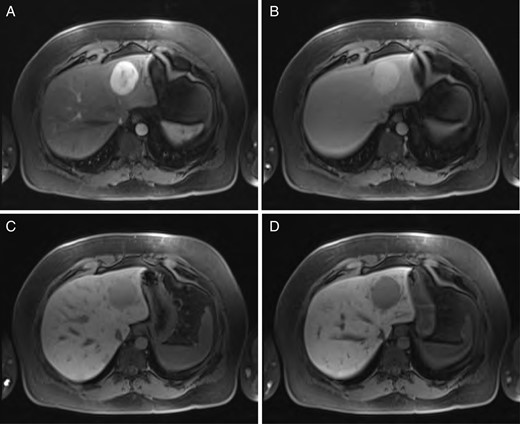

Sequential MRI imaging of HSFT: (A) T1 arterial phase, (B) T1 60-s delay phase, (C) T1 postcontrast phase and (D) T1 hepatographic phase.

A 40-year-old male underwent computed tomography (CT) scan of the chest for atypical chest pain, which revealed an indeterminate 3-cm lesion in the right liver. He subsequently underwent triple-phase CT, which revealed two separate lesions: a 4.3 × 5.3-cm discrete mass in the left liver (Segment 2) and a 2.3 × 3.7-cm lobular, partially exophytic hypodense lesion in the right liver (Segment 6). On the delayed phase, the periphery of the right posterior hepatic mass was isodense with the rest of the liver parenchyma, but the central portion remained hypodense. Based on these findings, the right-sided lesion was felt to be a hemangioma, but the findings were still inconclusive regarding the left-sided lesion. Magnetic resonance imaging (MRI) was performed with intravenous gadoxetic acid, a hepatocyte-specific contrast agent. The lesion in Segment 2 was hypointense on precontrast T1, hyperintense on T2-weighted images, and showed avid enhancement on the arterial and portal venous phases. There was a delayed washout on the hepatographic phase. Although nonspecific, this was felt to be most consistent with an adenoma. The right-sided lesion showed postcontrast gradual enhancement with centripetal fill-in, reinforcing the diagnosis of hemangioma (Figs 1 and 2).